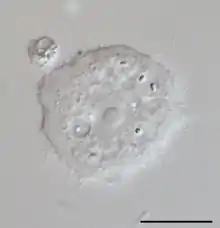

In cases of keratitis, diagnosis is typically achieved through evaluation of corneal scrapings. Scrapings are taking from the cornea, and plated on agar for culture, and also can be stained using Gram stain and Giemsa stain to differentiate between bacterial keratitis and AK. To culture Acanthamoeba, scrapings are placed on a non-nutrient agar saline plate seeded with a gram-negative bacteria such as E. coli. If Acanthamoeba are present, they will reproduce readily and become visible on the plate under 10–20 times objective on an inverted microscope. Polymerase chain reaction (PCR) can be used to confirm a diagnosis of Acanthamoeba keratitis, especially when contact lenses are not involved.[23] Confocal microscopy is a non-invasive technique that allows visualization of Acanthamoeba in vivo in cases in which corneal scraping, culture, and cytology do not yield a diagnosis.[24]